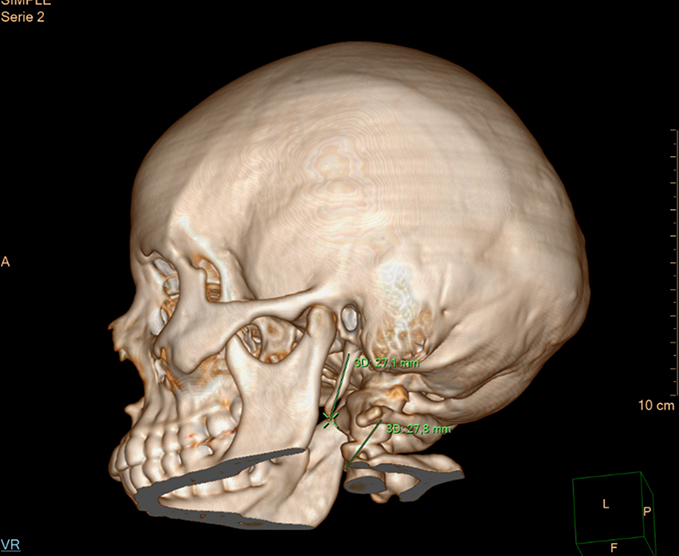

- TC cráneo (Simple y contrastada)

- Maxilares o cara